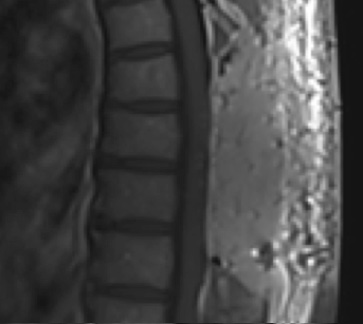

Preoperative MRI T1w demonstrating a large enhancing tumor with severe cord compression

Postoperative MRI T1w demonstrating a gross total resection